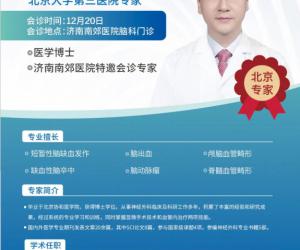

- 12-18北医三院脑科专家尹晓亮博士12月20日莅临南郊医院 疑难脑病会诊再启

- 12-11脑血管病患者福音!北大三院尹晓亮博士12月13日莅临济南南郊医院开展专家会诊

- 11-14好消息!北京脑科专家尹晓亮博士来济南南郊医院会诊啦!

- 11-11北医三院脑科专家尹晓亮博士加盟济南南郊医院 齐鲁百姓家门口享顶尖诊疗

- 11-08重磅官宣!北医三院尹晓亮博士加盟济南南郊医院守护脑健康

- 11-06北医三院脑科专家尹晓亮博士加盟南郊医院守护泉城百姓“脑健康”

- 12-18北医三院脑科专家尹晓亮博

- 12-11脑血管病患者福音!北大三